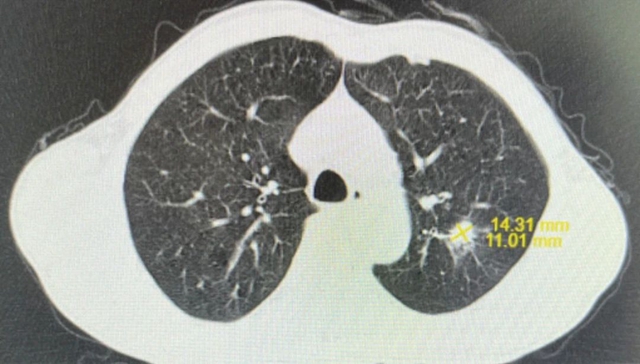

经积极治疗后,李大叔颈部包块基本消失,肺部病灶明显缩小,尤其是放疗期间李大叔头颈部放射性皮炎、放射性口咽炎轻微,生存质量高。

治疗3月后,李大叔复查胸部CT与上次比较,肺部结节缩小,大小约1.6×1.3cm²;复查鼻咽部MRI提示:鼻咽部病灶明显缩小,右侧咽旁间隙肿大淋巴结未见显示,颈部双侧淋巴结数量减少、体积缩小。